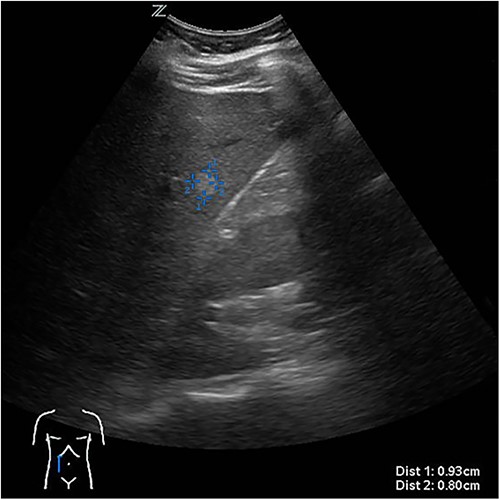

Due to persistent pain, the decision was made to perform a laparoscopic cyst deroofing. In an intraoperatively performed ultra sound (Fig. 3), however, a complex septation was seen so that the decision was made to perform a tru-cut biopsy in order to definitively rule out malignancy.

Intraoperative ultrasonographic localization of the liver cyst.